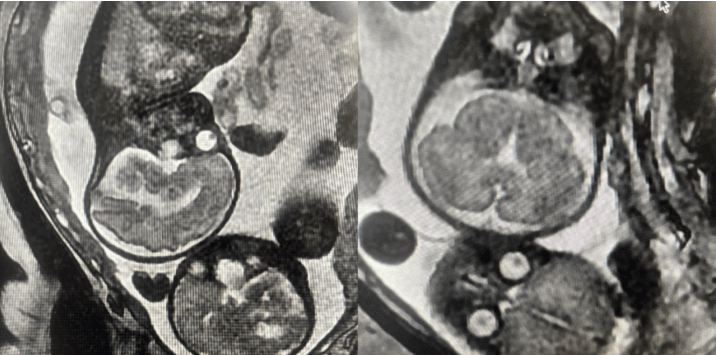

7月17日下午,宝鸡市妇幼保健院医学影像科成功为一名29+1周双胎妊娠孕妇完成了胎头核磁共振检查。此次检查不仅精准获取了胎儿颅脑影像,为临床诊疗提供了关键依据,也显示了该院在妇产科影像诊断领域的技术实力。

为保障检查的顺利与安全,医学影像科联合产科制定了个性化诊察方案,影像医生凭借丰富经验和精湛技术,耐心指导孕妇调整体位,密切监测体征状态,严格控制扫描参数,确保影像清晰准确。同时,考虑到孕妇的紧张情绪,医护人员全程给予心理安抚,有效缓解孕妇焦虑。最终,检查精准得出结果:胎儿1脐绕颈一周,胎儿2双侧侧脑室增宽。

高质量的影像数据清晰呈现了两个胎儿的颅脑形态、脑实质结构等关键信息,为临床医师评估胎儿发育状况、制定科学治疗方案提供了有力支撑。